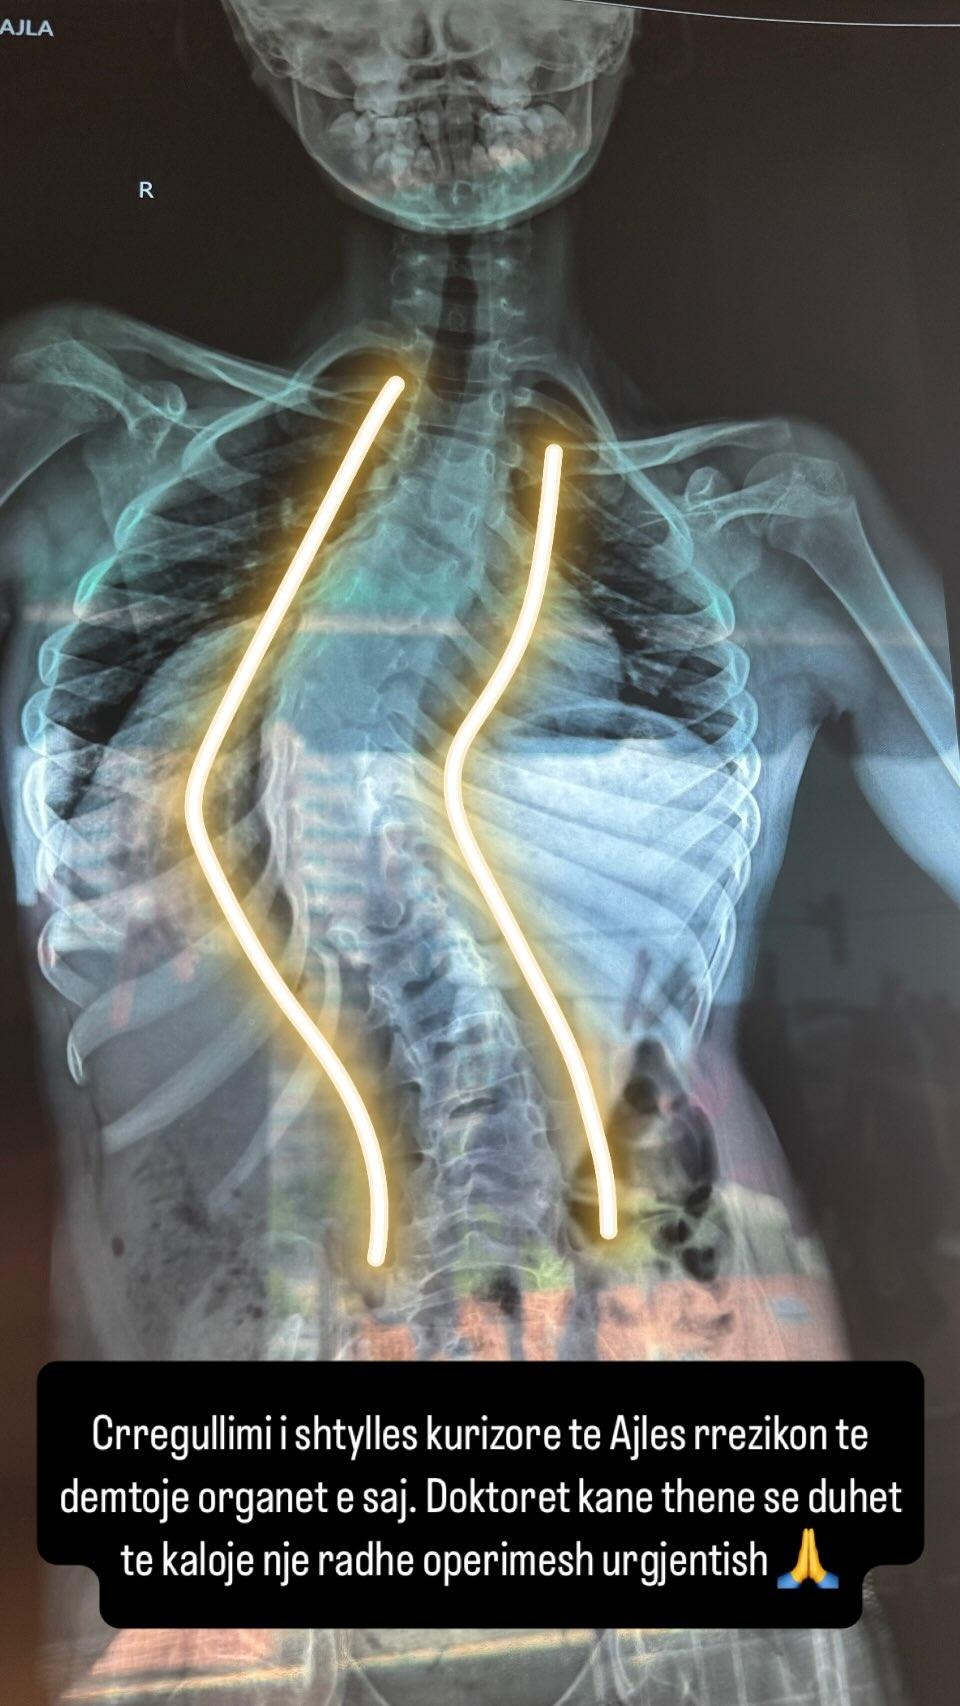

6 muaj pas operacionit, u shfaq skolioza. Kur Ajla ishte vetëm 4 vjeçe, iu desh të mbante një bust të fortë për shpinën, të cilin e mbajti për 5 vite me radhë, pasi doktorët na thanë se gjendja po përkeqësohej.

Six months after the surgery, scoliosis appeared. When Ajla was just 4 years old, she had to wear a hard back brace, which she wore continuously for 5 years, because the doctors told us her condition was getting worse.